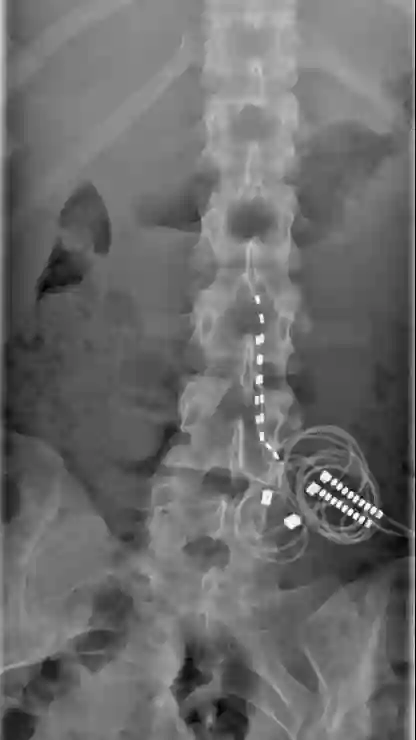

Stimwave Freedom-8A spinal cord stimulation (SCS)

Röntgenbild eines implantierten Wireless Stimwave Freedom-8A spinal cord stimulation (SCS) Systems.